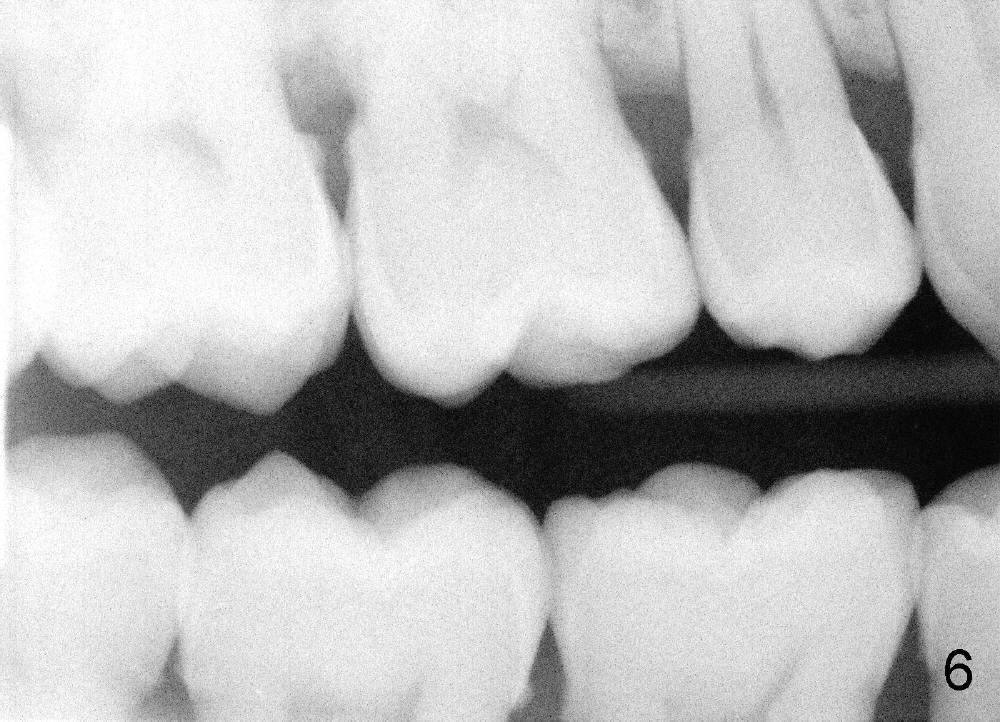

Forty-year-old man had ortho with extraction in his teens (Fig.1,2: B: bicuspid). Without wearing retainers, relapse occurs, particularly in the lower anterior. The lower left central incisor shifts labially with gingival recession (Fig.2,3). The attached gingiva is narrow for this incisor as compared to that of the neighboring tooth (Fig.4 between arrowheads). Although there is abundance of calculus, bone loss is mild to moderate (Fig.5-7). Scaling and root planing was finished today with schedule of perio maintenance every 3 months.

Both arches are narrow (Fig.1,2). Will be there space to move the lower left central lingually? Once the tooth is in normal position, gingival graft is performed to correct recession.